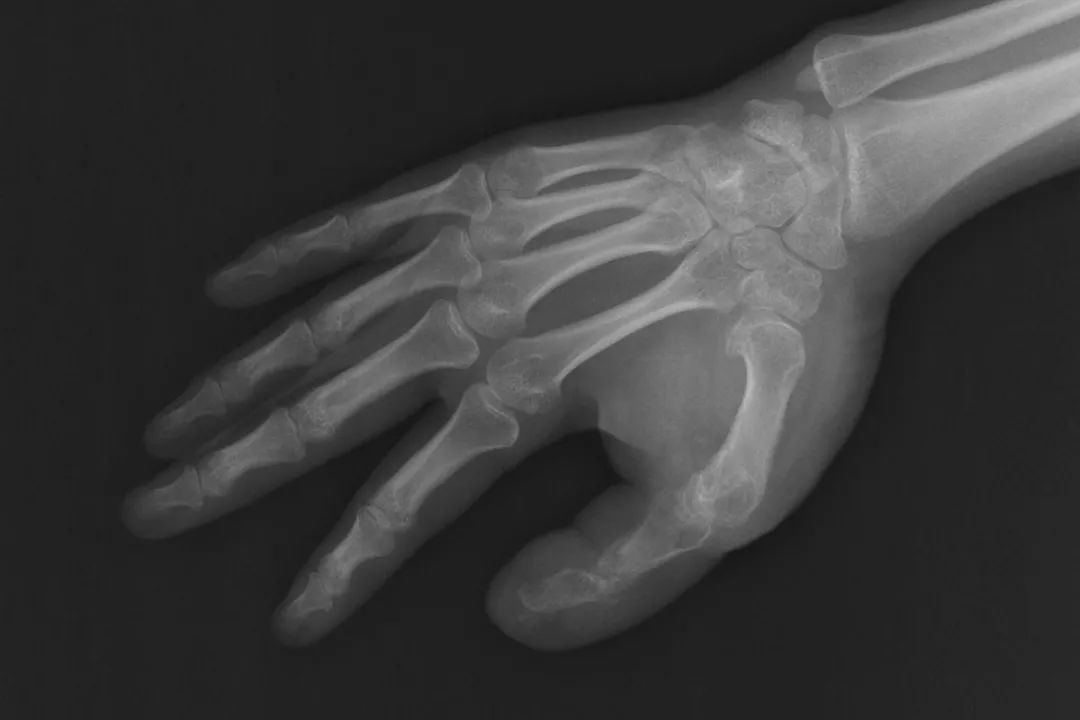

一期手术前,医生通过X线片测量手术切口并设计截骨方案,截骨后,拇指指骨已经接近正常大小。术后病理证实,何女士的巨指症属于典型的神经脂肪瘤病。通过制定个性化手术方案期并进行分期的手指外形的修复,目前巨大的手指外观得到了很好的改善。

杨蓊勃介绍说,巨指畸形是指一个或多个手指的所有组织结构,包括皮肤,皮下组织、肌腱、血管、神经、骨骼、指甲等均发生肥大,它可能仅表现为手指局部异常,也可能是各种先天畸形综合征的表现之一,可发生在一侧肢体或双侧,而这种肥大很少局限在手指,常常涉及手掌,有时包括整个手臂,甚至累及整个肢体呈半身发育过度。